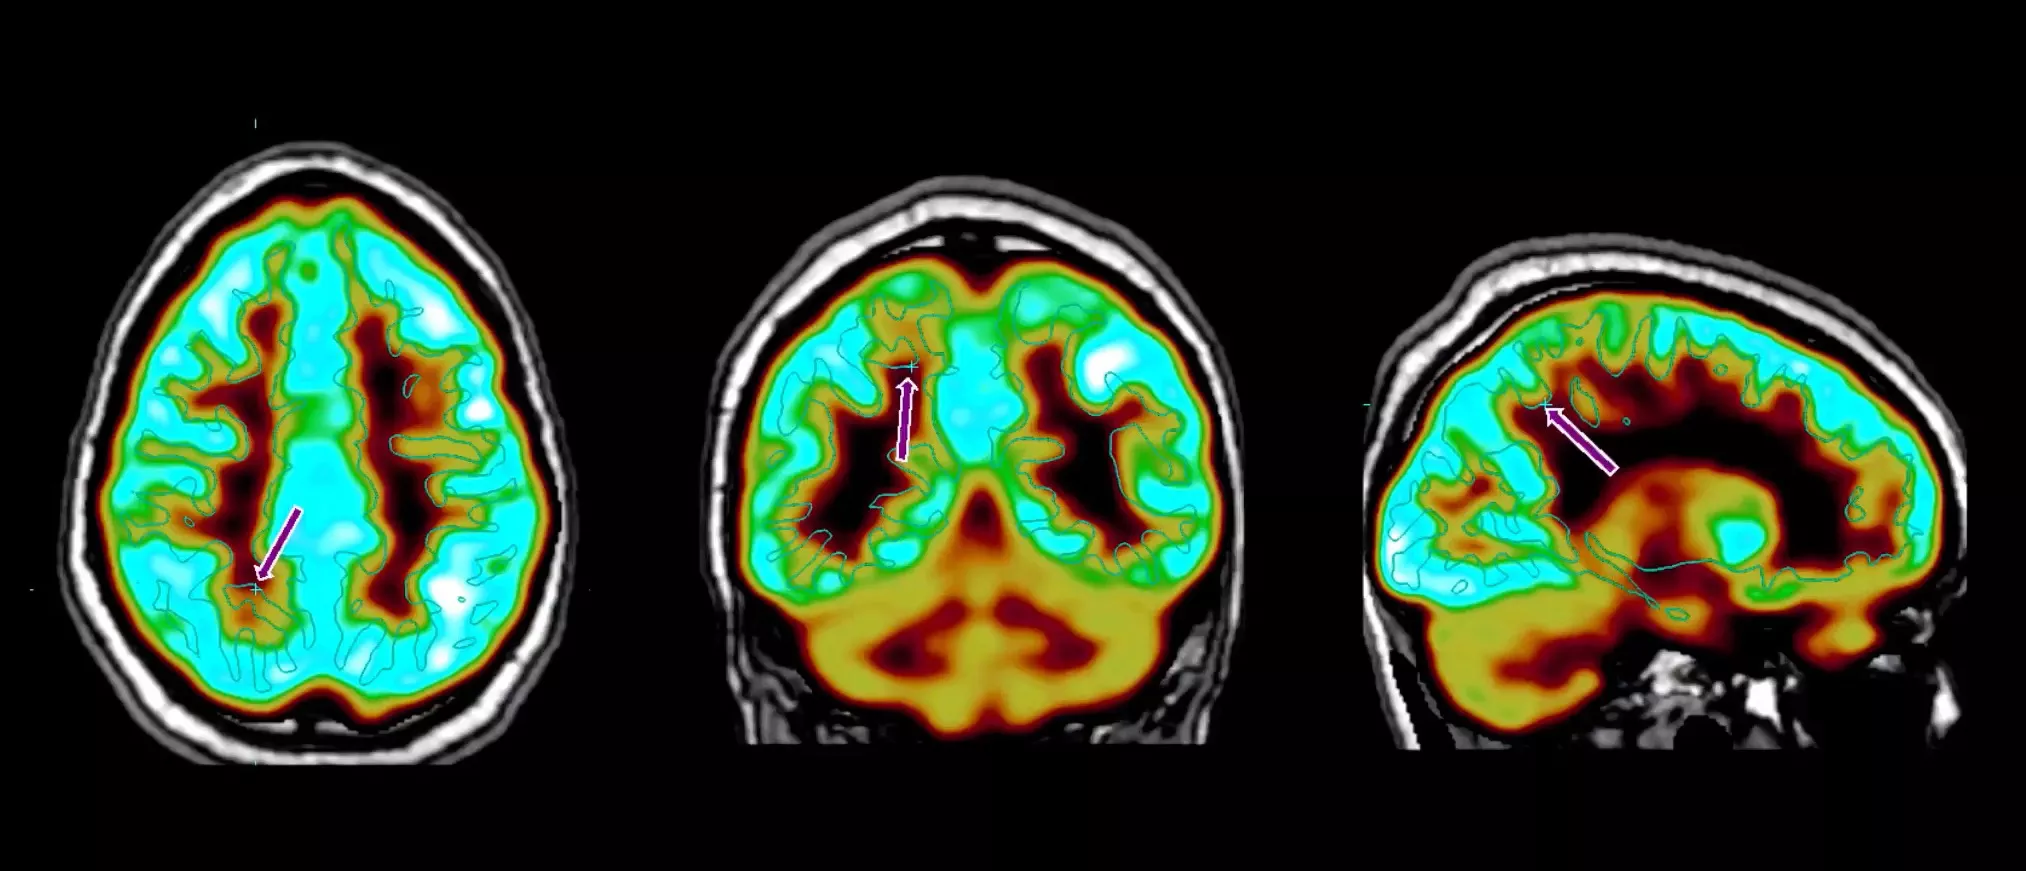

A brain scan showing epilepsy activity

Brain scan showing areas affected by epilepsy